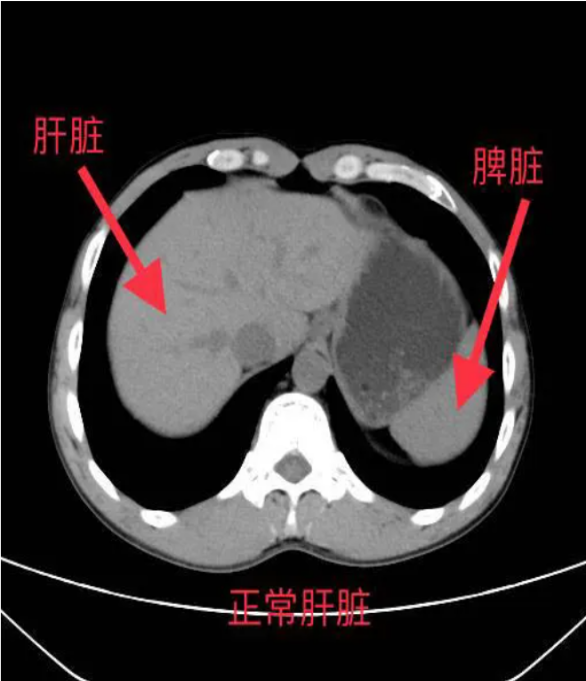

*肝臟密度降低:脂肪的CT值低于正常肝組織,因此脂肪肝在CT圖像上表現(xiàn)為肝臟密度普遍降低,與脾臟密度相比更加明顯。

*肝脾CT值比值:正常情況下,肝臟CT值高于脾臟,而脂肪肝患者的肝脾CT值比值會(huì)降低,甚至出現(xiàn)反轉(zhuǎn)。